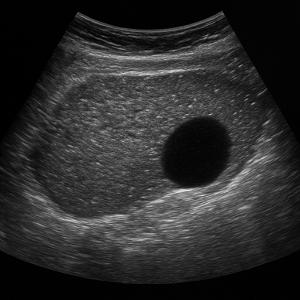

신장 결석, 신부전, 낭종

- 신장 결석

콩팥에 생긴 작은 돌들은 초음파에서 반짝이며 그림자를 동반해 쉽게 보일 수 있어요. - 신부전 (수신증 등)

소변이 막혀서 신장이 붓는 상태를 ‘수신증’이라고 하는데요, 초음파로 신장의 부종이나 이상을 확인할 수 있어요. - 신장 낭종이나 종양

주머니처럼 생긴 낭종이나 덩어리가 있으면 초음파로 확인 가능해요.